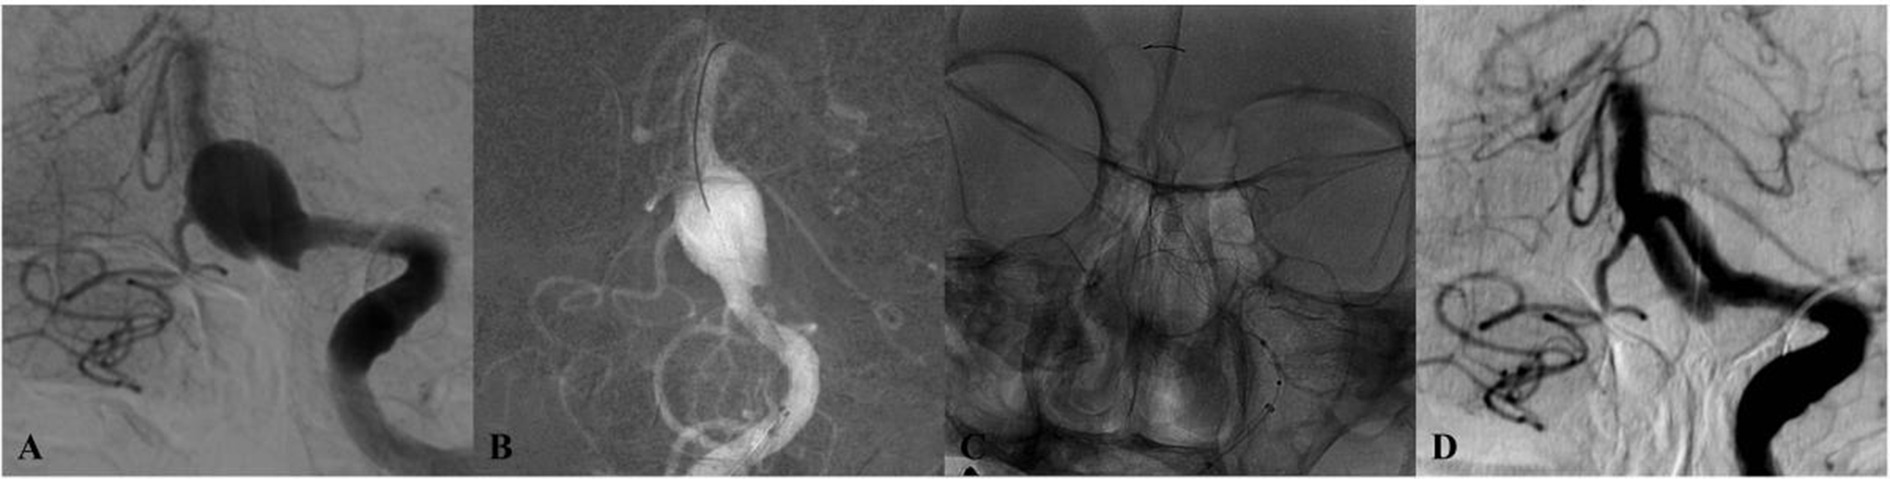

Four-panel medical imaging series of cerebral angiography depicting blood vessels in the brain. Panel A shows a significant aneurysm. Panels B and C illustrate the aneurysm after partial coiling. Panel D depicts the post-coiling result, showing reduced blood flow to the aneurysm site.

Figure 2. DSA of a patient from the 50–54 age group (Case 1) presenting with dizziness. (A) Preprocedural DSA demonstrates a saccular aneurysm of the basilar trunk measuring 5.3 × 3.7 mm. (B,C) Lateral and anteroposterior views immediately after deployment of a single PED across the aneurysm neck. (D) 12-month follow-up DSA confirms complete aneurysm occlusion.